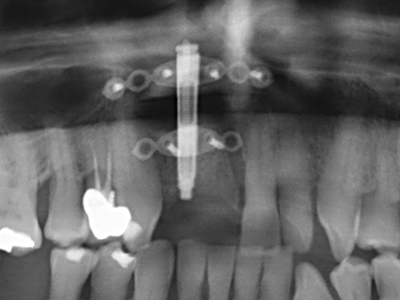

Костната тъкан е не само минерализирана структура, тя съдържа и съществено количество колагенови влакна. Това означава, че тя има не само добра компресивна сила, но и известна степен на гъвкавост, която може да се възприеме като предимство при извършване на костна аугментация. В класическата процедура по разширяване чрез костно разделяне, атрофиралият алвеоларен гребен е разделен надлъжно и внимателно разширен след достигане на подходящата остеотомна дълбочина (Фиг. 13-16), в идеалния случай без допълнително отстраняване на периостеума (Brugnami, Caiazzo et al. 2014, Stricker, Fleiner et al. 2014). Системите с винт и пластини с увеличаване на разстоянието при разширяване са доказали ефективността си при разделяне на двете костни ламели, оставайки под прага на фрактурите. В общи линии, оставащата ширина на костта от поне 3–4 mm е задължителна (Chiapasco, Zaniboni et al. 2006), за да се гарантира добра гъвкавост и достатъчно костно покритие за бъдещото поставяне на импланти. Ако е необходимо, вертикалната остеотомия на едната или двете страни може да подобри гъвкавостта. Комбинацията с допълнителни техники за аугментация, особено в букалната страна, е описана като алтернатива на класическата техника.

Процедурата по разделяне е атравматична и няма голяма загуба на пространство, използвайки пиезотриони, и няма значителна разлика между импланти в разделени челюсти и импланти в алвеоларния гребен без костен дефицит (Chiapasco, Zaniboni et al. 2006, Danza, Guidi et al. 2009). Въпреки това, важно е да има достатъчно и продължително охлаждане, особено при ограничено и дълбоко разделяне, за да се избегне термичен стрес в апикално-остеотомните зони.